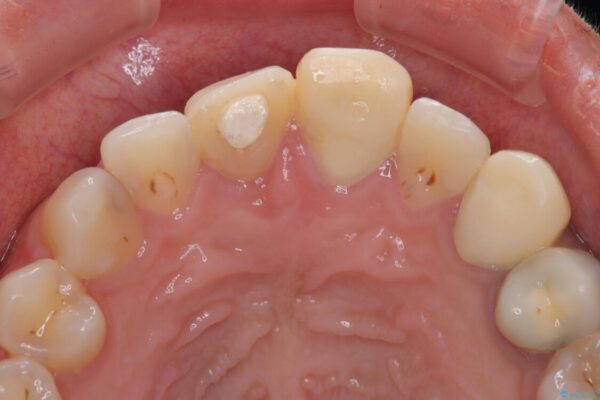

治療途中

• 「抜歯してブリッジ」と言われた20代女性が選んだ治療とは|たった4か月で自然な笑顔に抜歯即時インプラント+審美補綴の症例 治療途中画像